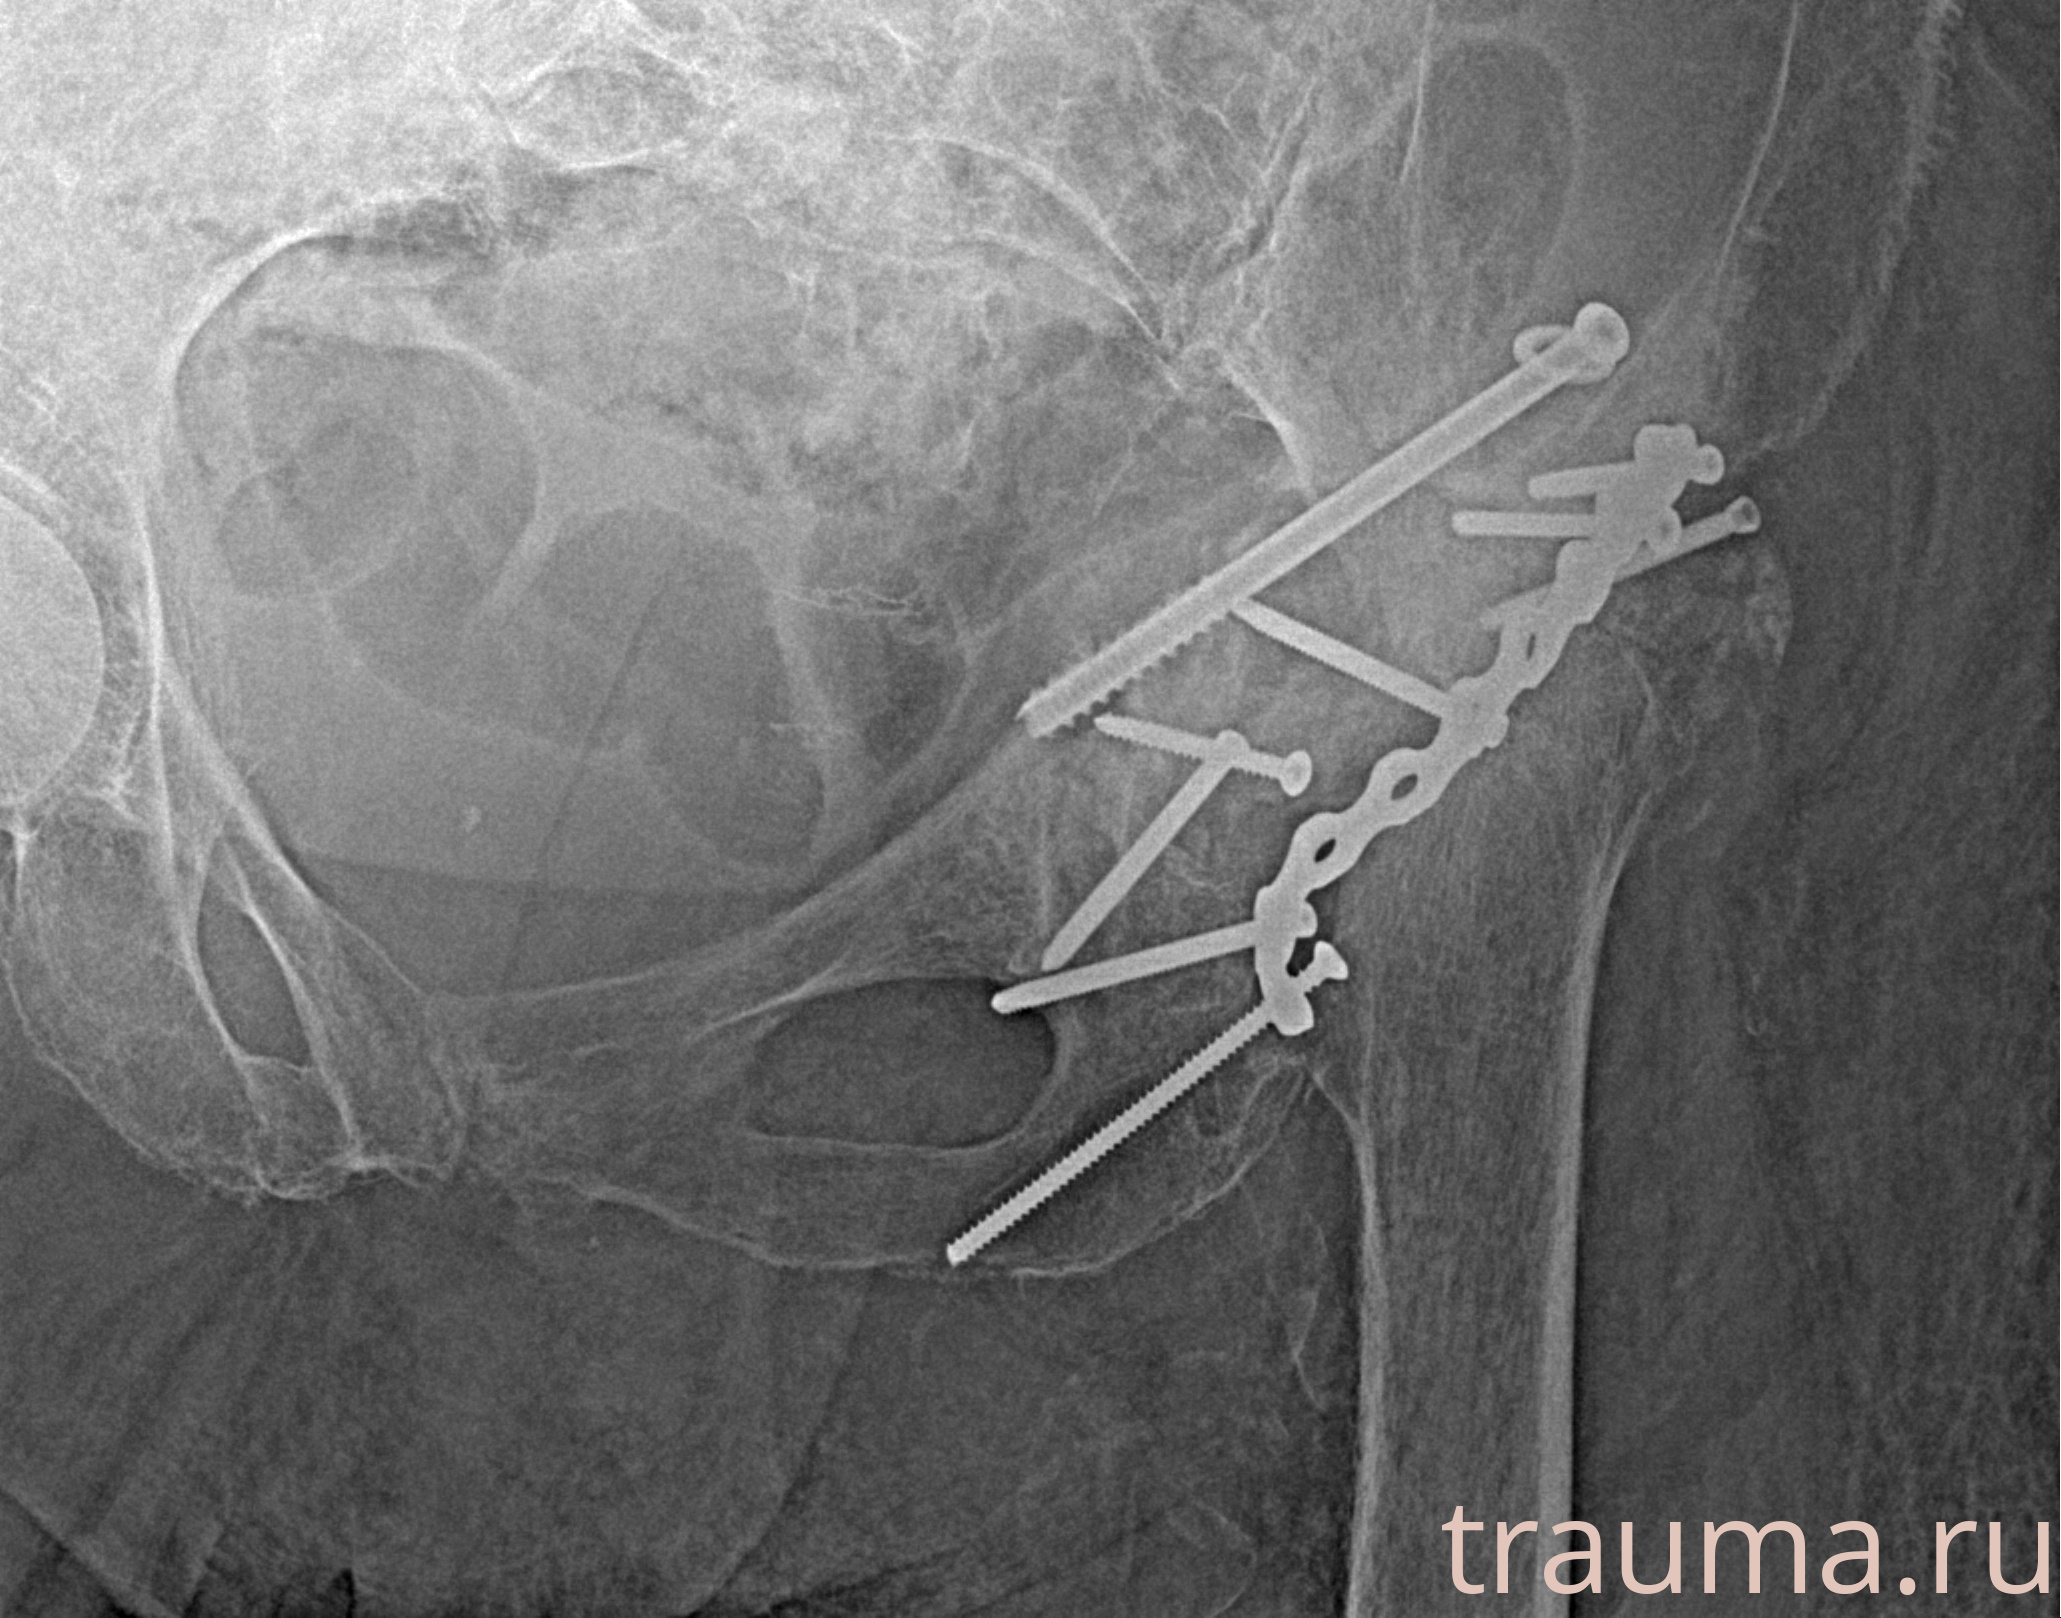

Рентгенограммы

Рентген на дому: по вашему адресу приезжает врач-рентгенолог, травматолог-ортопед с мобильным рентгеновским аппаратом, проводит диагностику травмы или заболевания, делает необходимые рентгенограммы, дает рекомендации по дальнейшему лечению. Получить качественные снимки в домашних условиях возможно благодаря уникальной методике, разработанной МосРентген Центром для института  Склифосовского